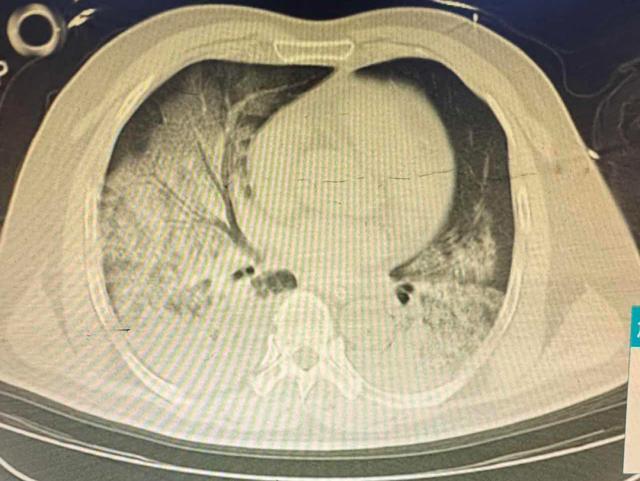

1月23日夜间,一名61岁男性患者从安化转入益阳市中心医院急诊。患者因严重溺水导致多脏器功能衰竭,外院呼吸机已难以维持氧合,病情极度危重。急诊完善胸部CT提示双肺大面积渗出病变超过80%,患者随即紧急转入重症医学科(ICU)。

患者入ICU后,医护团队立即予呼吸机辅助通气、去甲肾上腺素等药物维持生命体征。主治医师张林接诊后发现,常规机械通气已无法维持有效氧合,患者氧合指数最低仅38,生命垂危。